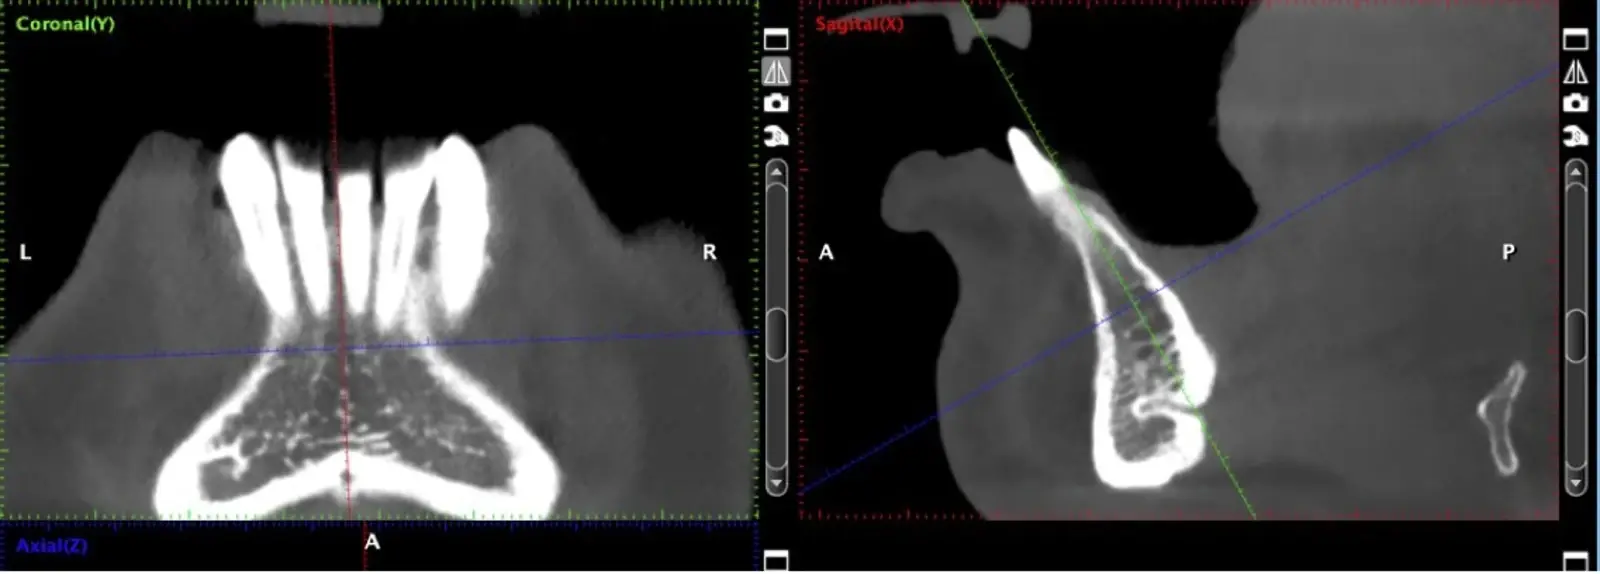

El hueso autógeno, considerado como el “gold stándard” para la regeneración ósea, no produce reacciones inmunológicas y contiene componentes osteogénicos, osteoinductores y osteoconductores.7,8 Suele obtenerse en bloques y las zonas dadoras intraorales de elección son la sínfisis mentoniana y la rama mandibular.9

La literatura menciona varias complicaciones relacionadas con la extracción de injertos óseos, la mayoría de ellas asociadas con el corte y la manipulación de zonas próximas a estructuras de riesgo; entre las más comunes, las lesiones nerviosas con consecuente adormecimiento, molestias postoperatorias (abertura bucal limitada, sangrado, hinchazón y dolor) y problemas estéticos (cambios en el contorno del área donadora o recesión de tejidos blandos).10 Aunque los injertos de rama pueden presentar menos molestias postoperatorias, tienen un acceso quirúrgico limitado debido a la apertura bucal y el peligro potencial de lesionar el paquete vásculo-nervioso cercano.11

El uso de vibraciones ultrasónicas se introdujo por primera vez hace dos décadas para superar las limitaciones de la instrumentación tradicional.12,13 Altiparmak y cols.14 reportaron en su estudio que la cirugía piezoeléctrica redujo significativamente la incidencia de alteraciones sensoriales tanto de la piel como de la mucosa oral, y redujo también el daño pulpar en los dientes adyacentes, sobre todo en los injertos sinfisiarios.

La osteotomía con insertos de piezoeléctrico nos permite un corte más definido con menor pérdida de hueso residual, ya que los insertos son extremadamente finos.